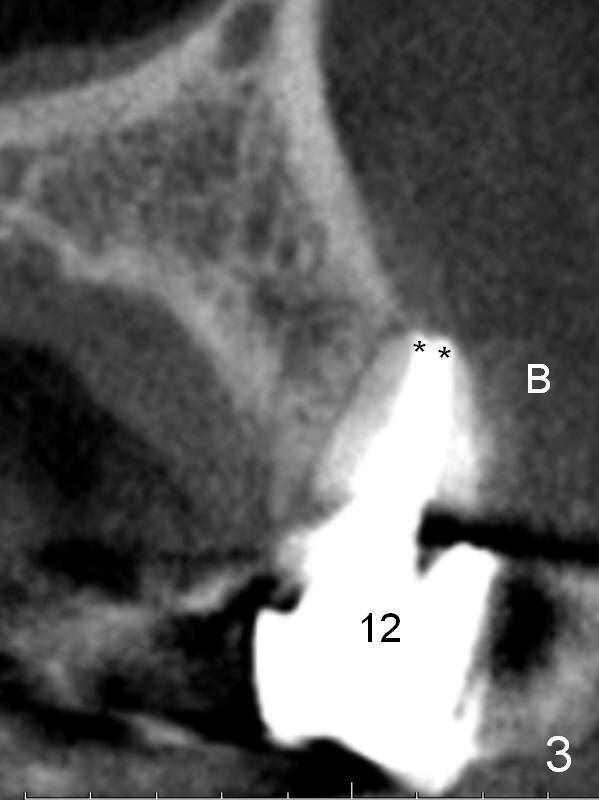

A 57-year-old lady had poor dentition, including periapical radiolucency of the tooth #12, 8 years ago (Fig.1 *, 2007).  After comprehensive treatment, the pathology is apparently under control (Fig.2 <, 2011).  CBCT shows the pathology not completely resolved (Fig.3,4, coronal section, 2012).  Early this year, there was sign of crack tooth at #12 (Fig.5 arrowheads).  Last Saturday she returned because of dislodgement of the crown and post.  The tooth is found to be non salvageable.

A 4.5x14 mm bone-level or 4.5x17 mm tissue-level implant appears to be appropriate for the site according to the PA (Fig.6,7).  CBCT shows that there is enough bone to place a 4.5x20 mm tissue-level implant (Fig.8).  This is more appropriate, considering the large radiolucency (Fig.5), the age of the patient (possibly osteoporosis), and the maxilla (bone softer than that of the mandible).  The implant will be supported by approximately 8 mm solid bone apically (Fig.8).

In addition, osteotomy will be under prep.  The depth of a 2 mm pilot drill, 2.5 mm and 3 mm reamers will be 20 mm, 17 mm and 14 mm, respectively.  A 4.5x20 mm tap will be inserted 17 mm before placing the corresponding implant.  Intraop PAs are to be taken following the pilot drill, tap and implant.